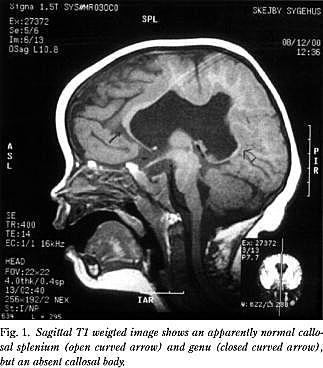

På grund af dysmorfologien og den forsinkede udvikling udførte man under anæstesi MR-scanning af cerebrum (Fig. 1 og Fig. 2 ). Scanningen afslørede et forstørret ventrikelsystem og septum pellucidum agenesia. Der fandtes mindre agenesi af begge temporalpoler. Corpus callosum var dysgenetisk med fraværende corpusdel. Der sås en sammenvoksning af den midterste del af de to storhjernehalvdele. Fissura sylvii fortsatte i en fissur frontoparietalt henover ventrikelsystemet og forbandt de to fissurer med hinanden. Der var ingen kortikale dysplasiforandringer eller heteropier. Der var normale myeliniseringsforhold og basalganglier. Billedet var foreneligt med middle interhemispheric fusion, også kaldet syntelencefali.